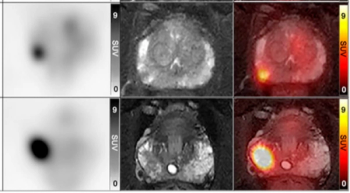

In a cohort of 85 patients with biomechanical recurrence of prostate cancer and PSA values less than 2 ng/mL, positive findings on PET imaging with PSMA-18F DCFPyL led to treatment changes in the majority of patients who had negative findings on conventional imaging, according to new research presented at the SNMMI conference.